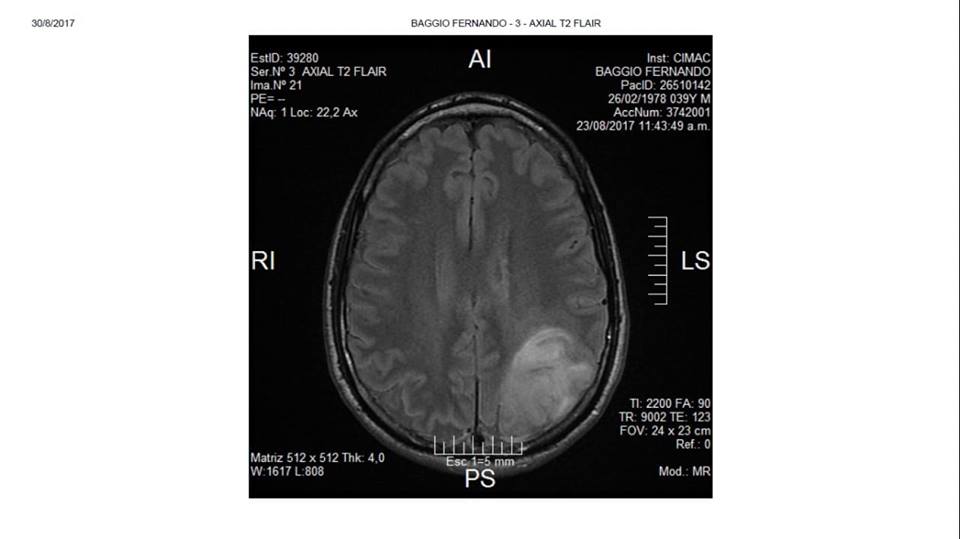

Por la falta de respuestas de la obra social, Fernando recurrió a la justicia porque en el único lugar donde pueden operarlo es en la Clínica Adventista Belgrano, de Buenos Aires. "Mi tumor no es visible y no tiene márgenes por eso, los médicos necesitan un resonador en la cirugía y esa clínica es la única en el país que lo tiene", describió y agregó que un total de 16 profesionales intervendrán en la operación, por la complejidad de la misma.